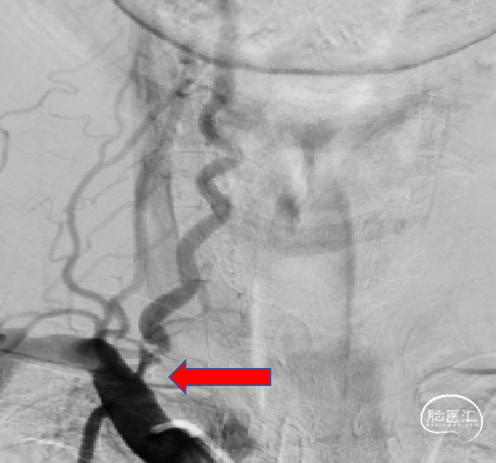

DSA:左右颈内动脉起始部均次全闭塞,血流缓慢,不能达到颅内,双侧均是眼动脉代偿颅内供血,且都能返流到C3段。

DSA:右侧椎动脉开口重度狭窄;左侧椎动脉纤细。

考虑椎动脉和锁骨下动脉的成角关系,选择经股动脉穿刺,患者仰卧位,麻醉到位,股动脉穿刺点消毒铺无菌巾,右股动脉穿刺置6F血管鞘,引入泥鳅导丝将5F造影导管置于主动脉弓完成全脑血管造影。造影确认右侧椎动脉开口重度狭窄。